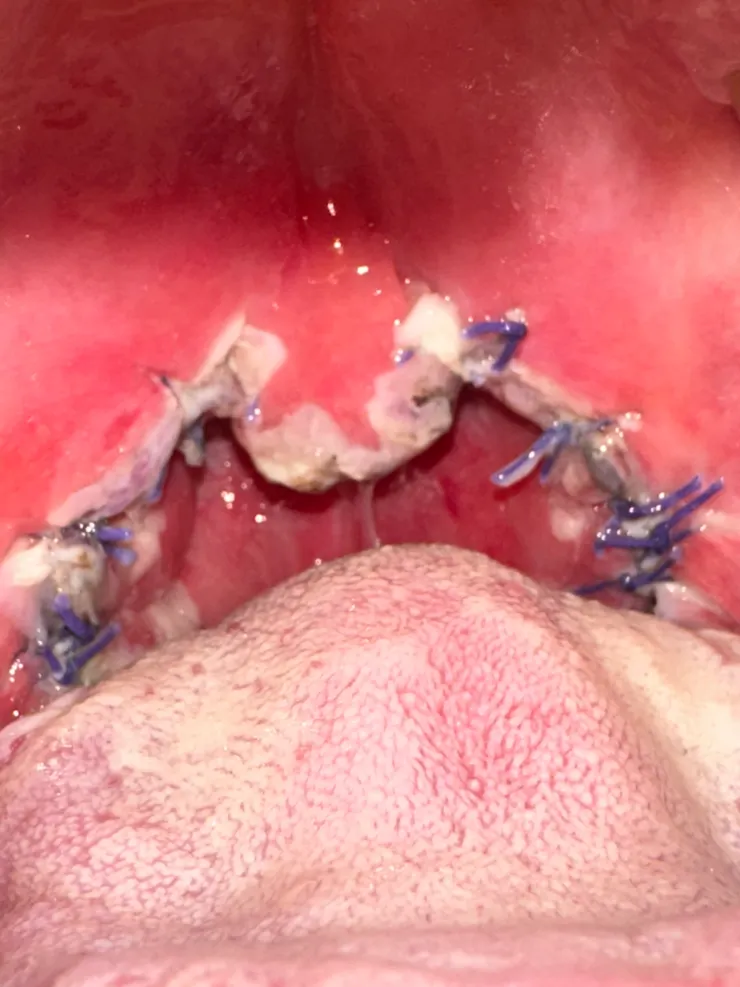

整個喉嚨都是縫線

醫生來 打開他手機的手電筒照我喉嚨縫線處

傷口會變成白色 再推掉

只剩下腫脹 縫線會自行吸收